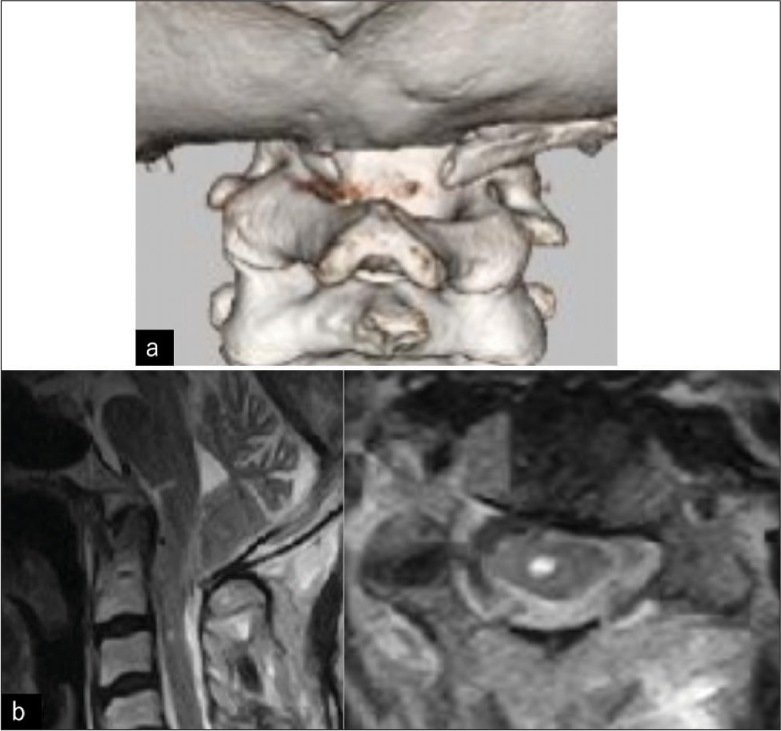

背景:咳嗽性晕厥、中枢性睡眠呼吸暂停(CSA)和伴有寰椎同化的Chiari 1型畸形(CM1)在成人中非常罕见。病例描述:一名48岁男性出租车司机晕倒。他的神经系统是完整的,但经多面体图检测,轻度睡眠呼吸暂停呈阳性。磁共振成像诊断为CM1伴脊髓空洞和寰枕。患者在7年后接受了大枕骨孔减压/C1椎板切除术,并保持完整。结论:1例48岁男性晕厥后出现咳嗽性晕厥、CSA和CM1;在枕骨大孔减压/C1椎板切除术后,患者在接下来的7年中保持神经系统稳定。

Case description: A 48-year-old male taxi driver fainted. He was neurologically intact, but tested positive for mild sleep apnea confirmed by a polysonogram. The magnetic resonance imaging diagnosed a CM1 with syringomyelia and atlas occipitalization. The patient underwent an uneventful foramen magnum decompression/C1 laminectomy and remained intact 7 years later.